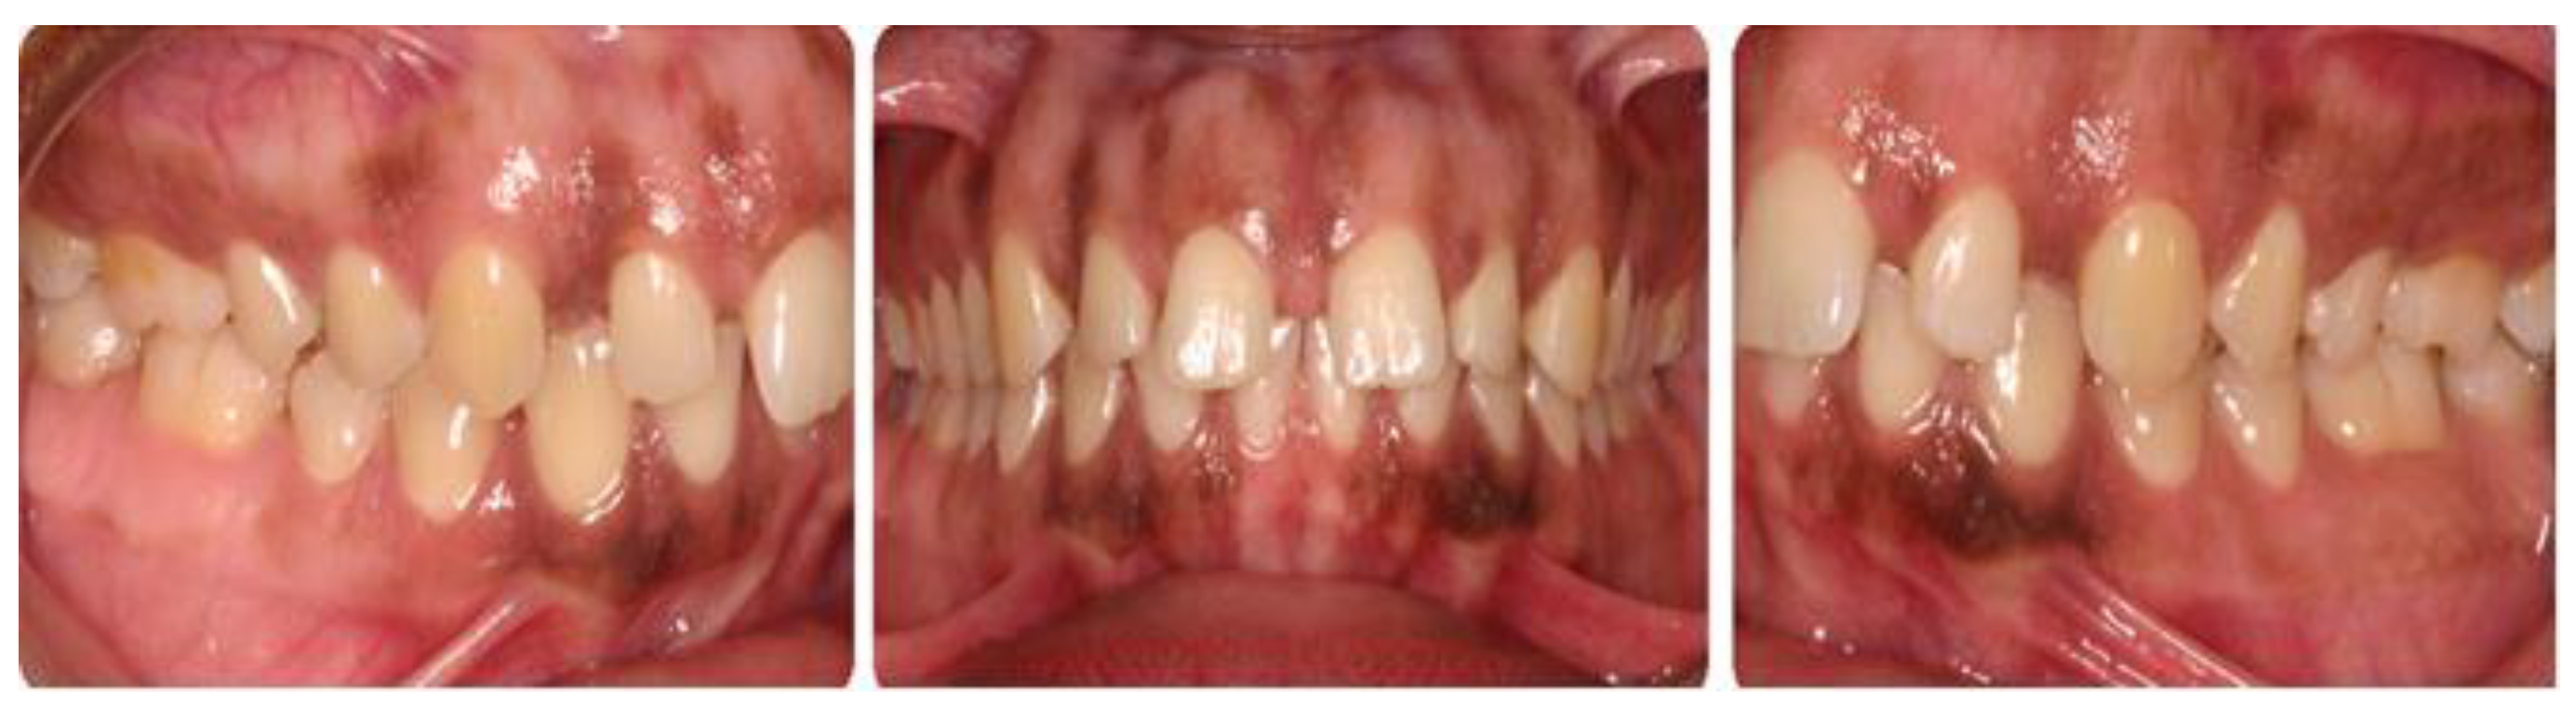

Figure 1. Pre-treatment intraoral pre-orthodontic treatment photograph.

Figure 2. Anterior view of the dentition with brackets bonded to the maxillary teeth with the nitinol wire at the first periodontal appointment displaying inflammatory gingival enlargement.

Figure 3. Anterior view at the re-evaluation phase (4 weeks after initial phase I periodontal prophylaxis treatment) at the second periodontal appointment.